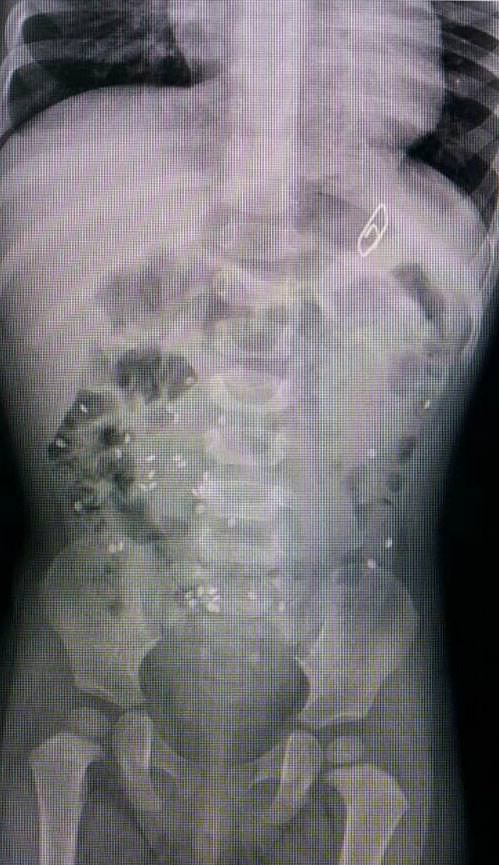

İzmir'deki Tepecik Eğitim ve Araştırma Hastanesi Çocuk Gastroenteroloji Bölümü'nün, yabancı cisim yutan çocukların nefes ve borusu ile midelerinden çıkarttığı, anahtarlık, madeni para, saat pili, ataç, çengelli iğne ve çivi gibi objeler görenleri şaşkına çevirdi.

"Çocukların nefes ve borusu ile midelerinden çıkartılan, anahtarlık, madeni para, saat pili, ataç, çengelli iğne ve çivi gibi objeler görenleri şaşkına çevirdi. "